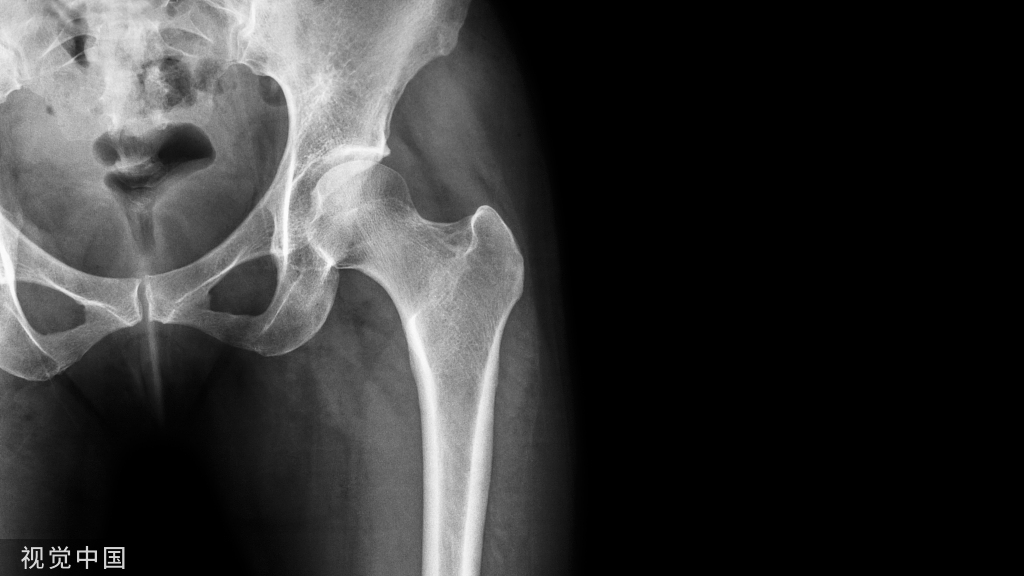

此类患者多见于女性,关节疼痛及行走乏力,跛行,MRI的T1WI显示股骨软骨下骨低信号,部分专科医师有时也将其诊断为ONFH,此是不对的,鉴别不难。拍摄双髋正位及蛙式位X线片示髋臼发育浅,股骨头包含不良等即可鉴别。